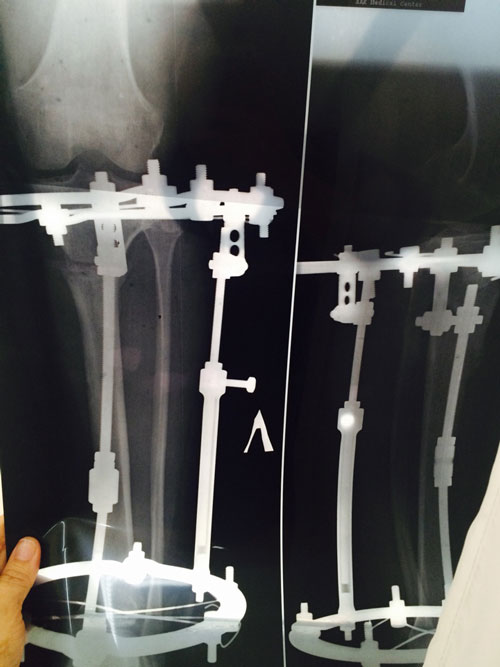

рентген в 90 дней.

Здравствуйте, Б.! Сращение идёт хорошо, но Вам ходить ещё месяц. в 120 дней ждём рентген.